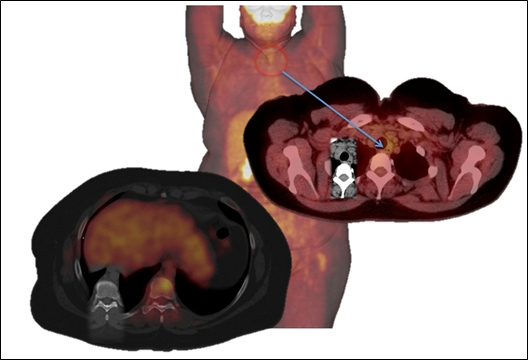

Muchas de las metástasis de los carcinomas papilares (CPT) bien diferenciados pueden progresar a carcinoma poco diferenciado de tiroides (CPDTC), lo que representa mayor avidez de glucosa demostrada por estudios PET con 18F-FDG; estos tumores son denominados no RAI(52). Los tumores no RAI (también llamados enfermedad RAI) pueden tener incapacidad para concentrar yodo o pueden tener un perfil genético similar al CPDTC sin demostrar el fenotipo clásico, es decir, que contradicen su verdadera naturaleza y aparecen bien diferenciados, pero presentan un perfil genético similar a un PDTC. Existe una cantidad importante de características de diferenciación presente entre los tumores primarios y las metástasis, que pueden reflejar la inestabilidad genética de estos tumores (fig. 1).

La mayoría de las metástasis en pacientes con 18F-FDG PET/CT positivo no RAI son de un subtipo histológico agresivo. Rivera y cols(53) analizaron la histopatología del tumor no RAI en el cáncer de tiroides y observaron que de 70 pacientes estudiados, el 37% demostraron un importante grado de discordancia morfológica entre el tumor primario y la metástasis. Esta diferencia entre el primario y la metástasis se refleja en el nivel genético, en el que aumenta el número de anomalías cromosómicas(54).

El carcinoma de células de Hürthle puede requerir tratamiento loco-regional más agresivo que otros tumores malignos de la tiroides, recomendándose siempre la evaluación exhaustiva de metástasis a distancia. El tumor muestra intensa captación de FDG, lo que significa que es muy ávido para la glucosa y permite valorar el compromiso metastásico a distancia con PET/CT(73).